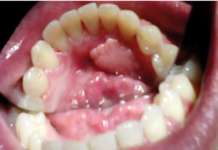

Il lavoro sinergico delle università in oggetto ha mostrato che i pazienti affetti da SIOD con mutazioni SMARCAL1 bi-alleliche nel 66,0% presentava anomalie dentali. Il 46,8% aveva microdonzia e il 52,3% aveva ipodonzia. Il numero di denti mancanti variava da 0 a 15, i premolari erano gli elementi più frequentemente assenti. Oltre ai denti piccoli o assenti, il 72,0% dei pazienti con SIOD presentava radici dei molari ipoplasiche. La sproporzione tra la corona del molare e le radici variava da quasi normale a grave. I premolari permanenti e i primi molari sono prevalentemente malformati, mentre gli incisivi e i canini di solito risultano nella norma.

La maggior parte dei denti presenta una colorazione nella norma tranne in alcuni casi in cui si evidenziano delle opacità.

Come suggerito da Fonseca (2000), il fenotipo dentale in SIOD assomiglia a quello della dentinogenesi imperfetta (DI) di tipo II, che è caratterizzato da denti opalescenti o traslucidi con alterazione cromatica, superficie abrasa, radici corte ristrette e obliterazione delle camere pulpari (Shields et al, 1973). Inoltre, come la SIOD, il tipo DI II interessa sia la dentizione decidua che quella permanente (Sclare, 1948). Tuttavia, a differenza del tipo DI II, i denti SIOD presentano raramente decolorazione, ipoplasia dello smalto e dentina morbida. I denti di tutti i pazienti SIOD oggetto della ricerca presentavano una opacità tendenzialmente normale. In base alle nostre attuali conoscenze il fenotipo dentale di SIOD è unico.